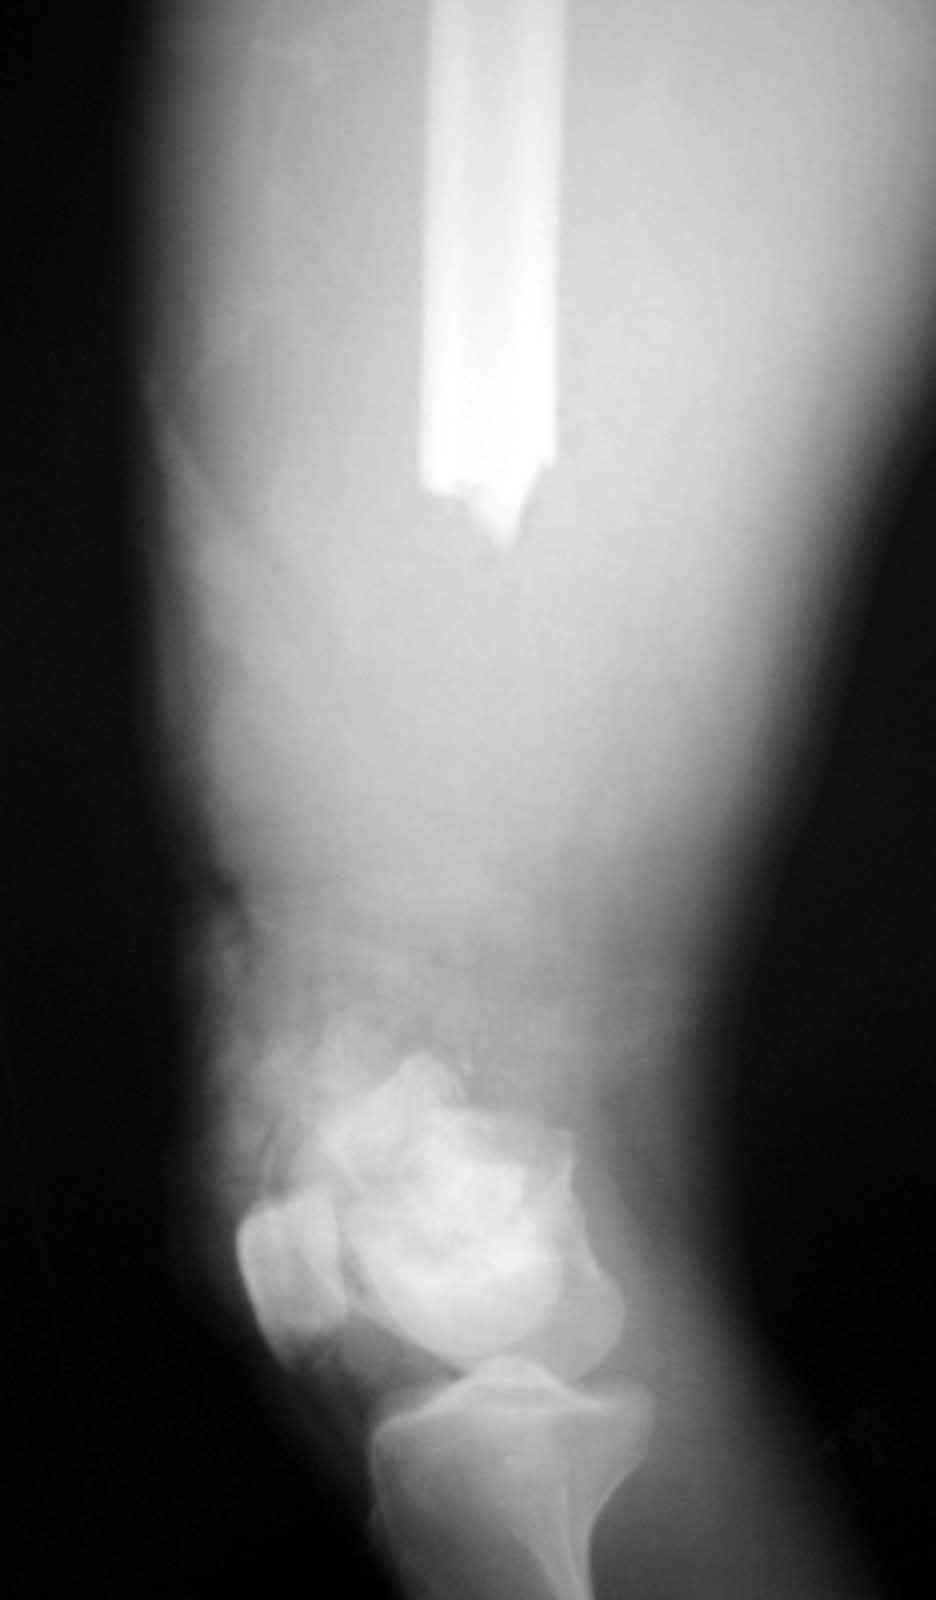

18 ys. old boy with motorcycle accident lost the distal 1/2 of his femur at the scene of the accident.

Debridment and ex. fix done immediately.